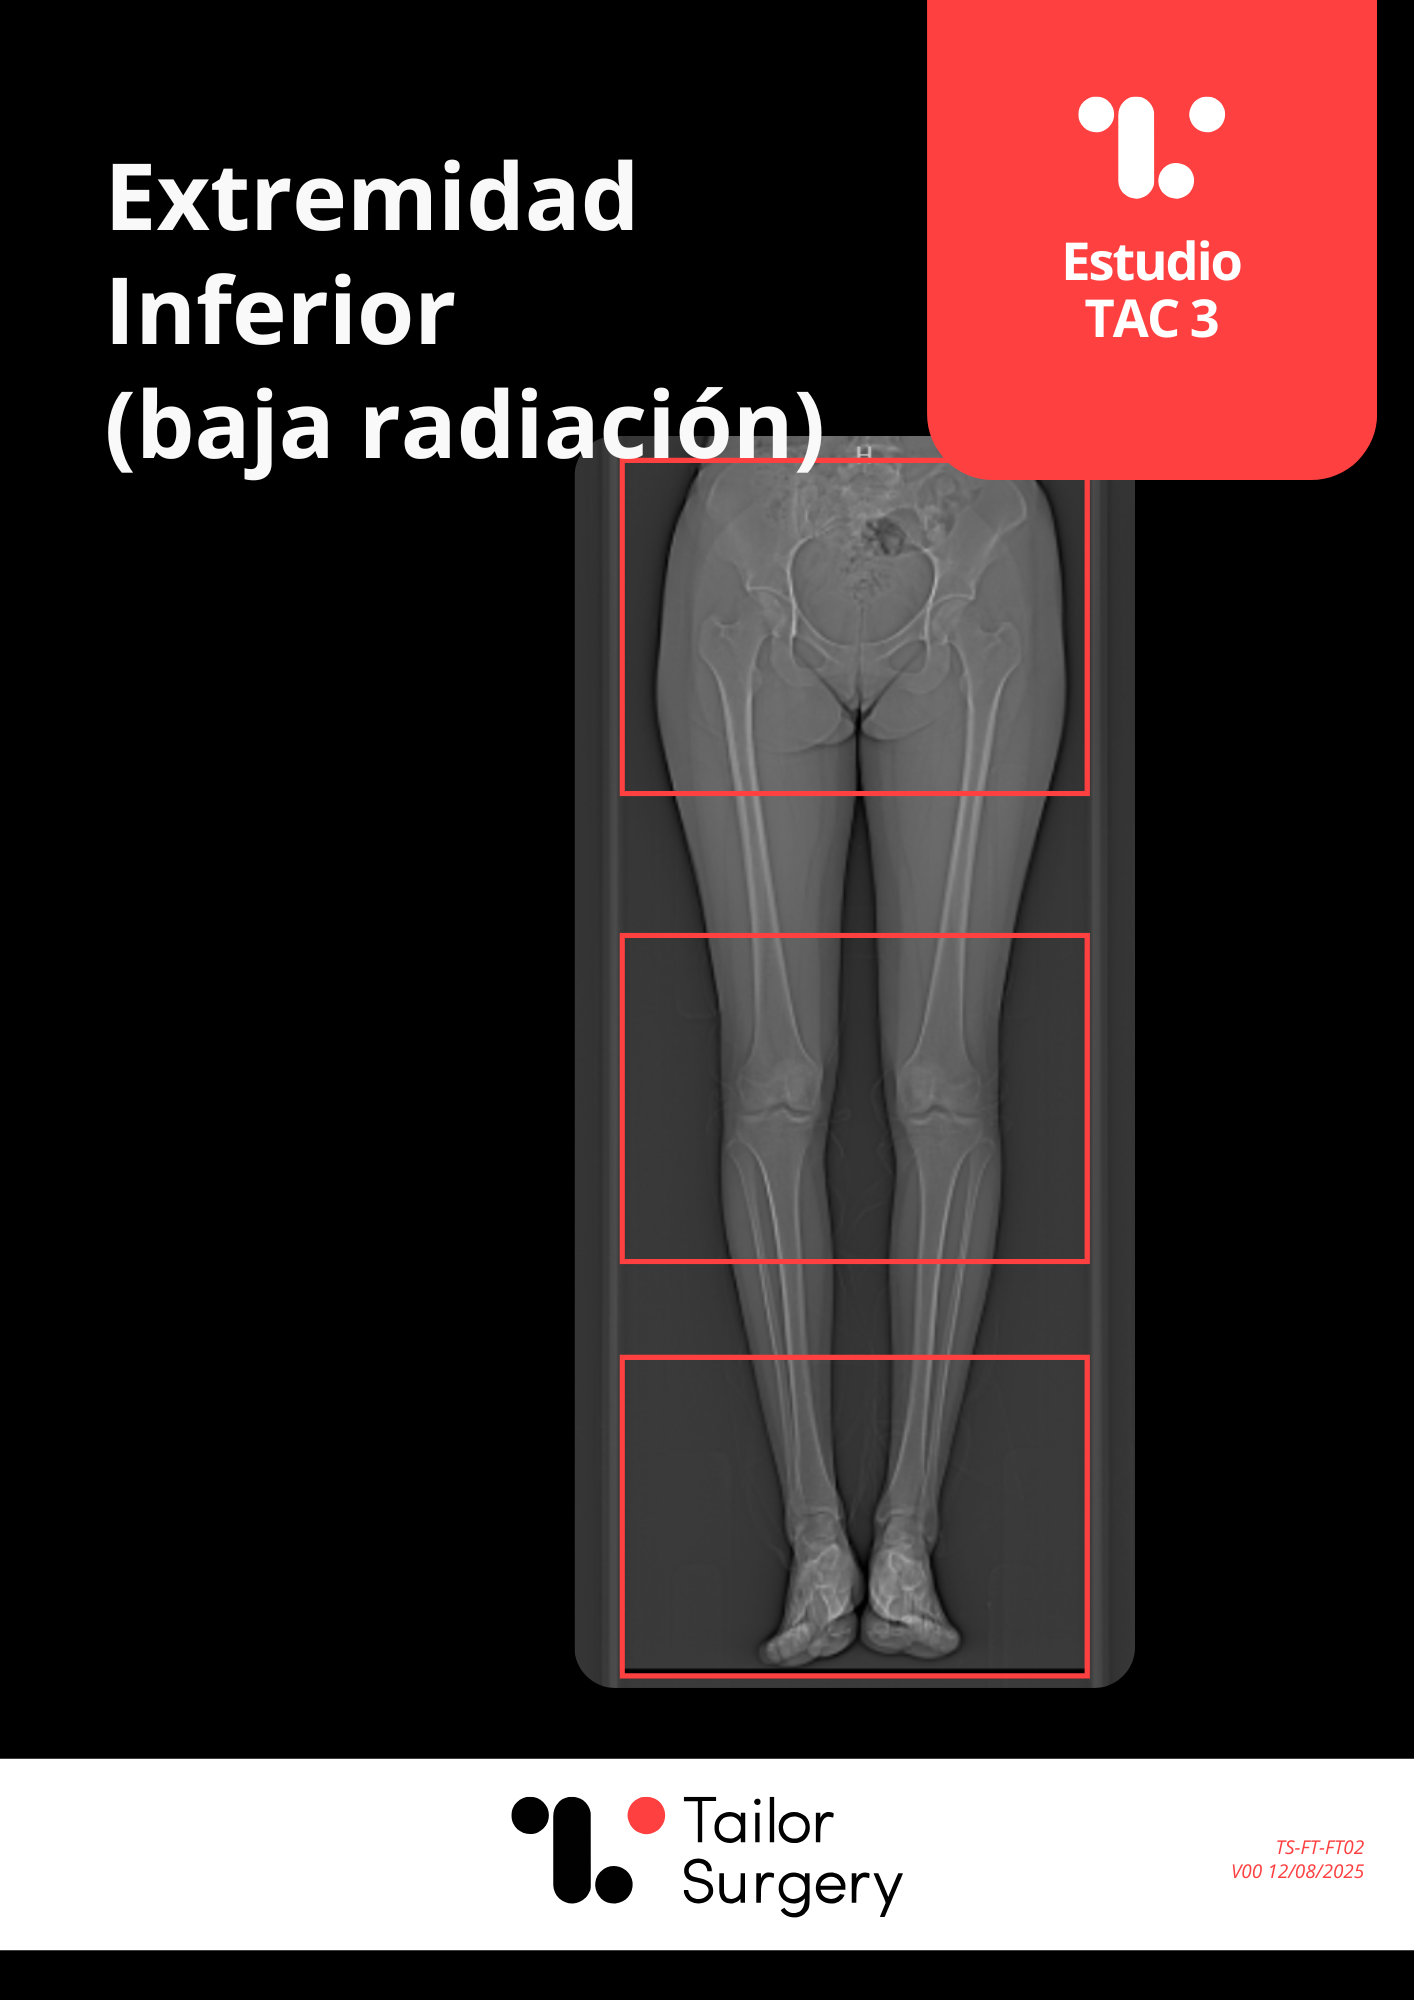

Columna Torácica-Lumbar

Este documento define el protocolo para los siguientes procedimientos: • Fusión Fusión Torácica y Lumbar